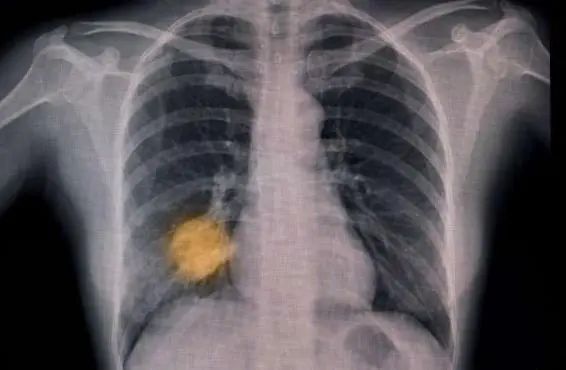

另一項進行中的試驗正在追蹤英國6家醫(yī)院的15萬名患者,測試AI能否根據(jù)胸部X光片作出肺癌早期診斷,發(fā)現(xiàn)哪些患者需要當(dāng)天接受計算機斷層掃描(CT)。

人工智能工具的試驗和兩年一次的篩查有望幫助人們更早地發(fā)現(xiàn)肺癌。

圖片來源:《自然·醫(yī)學(xué)》